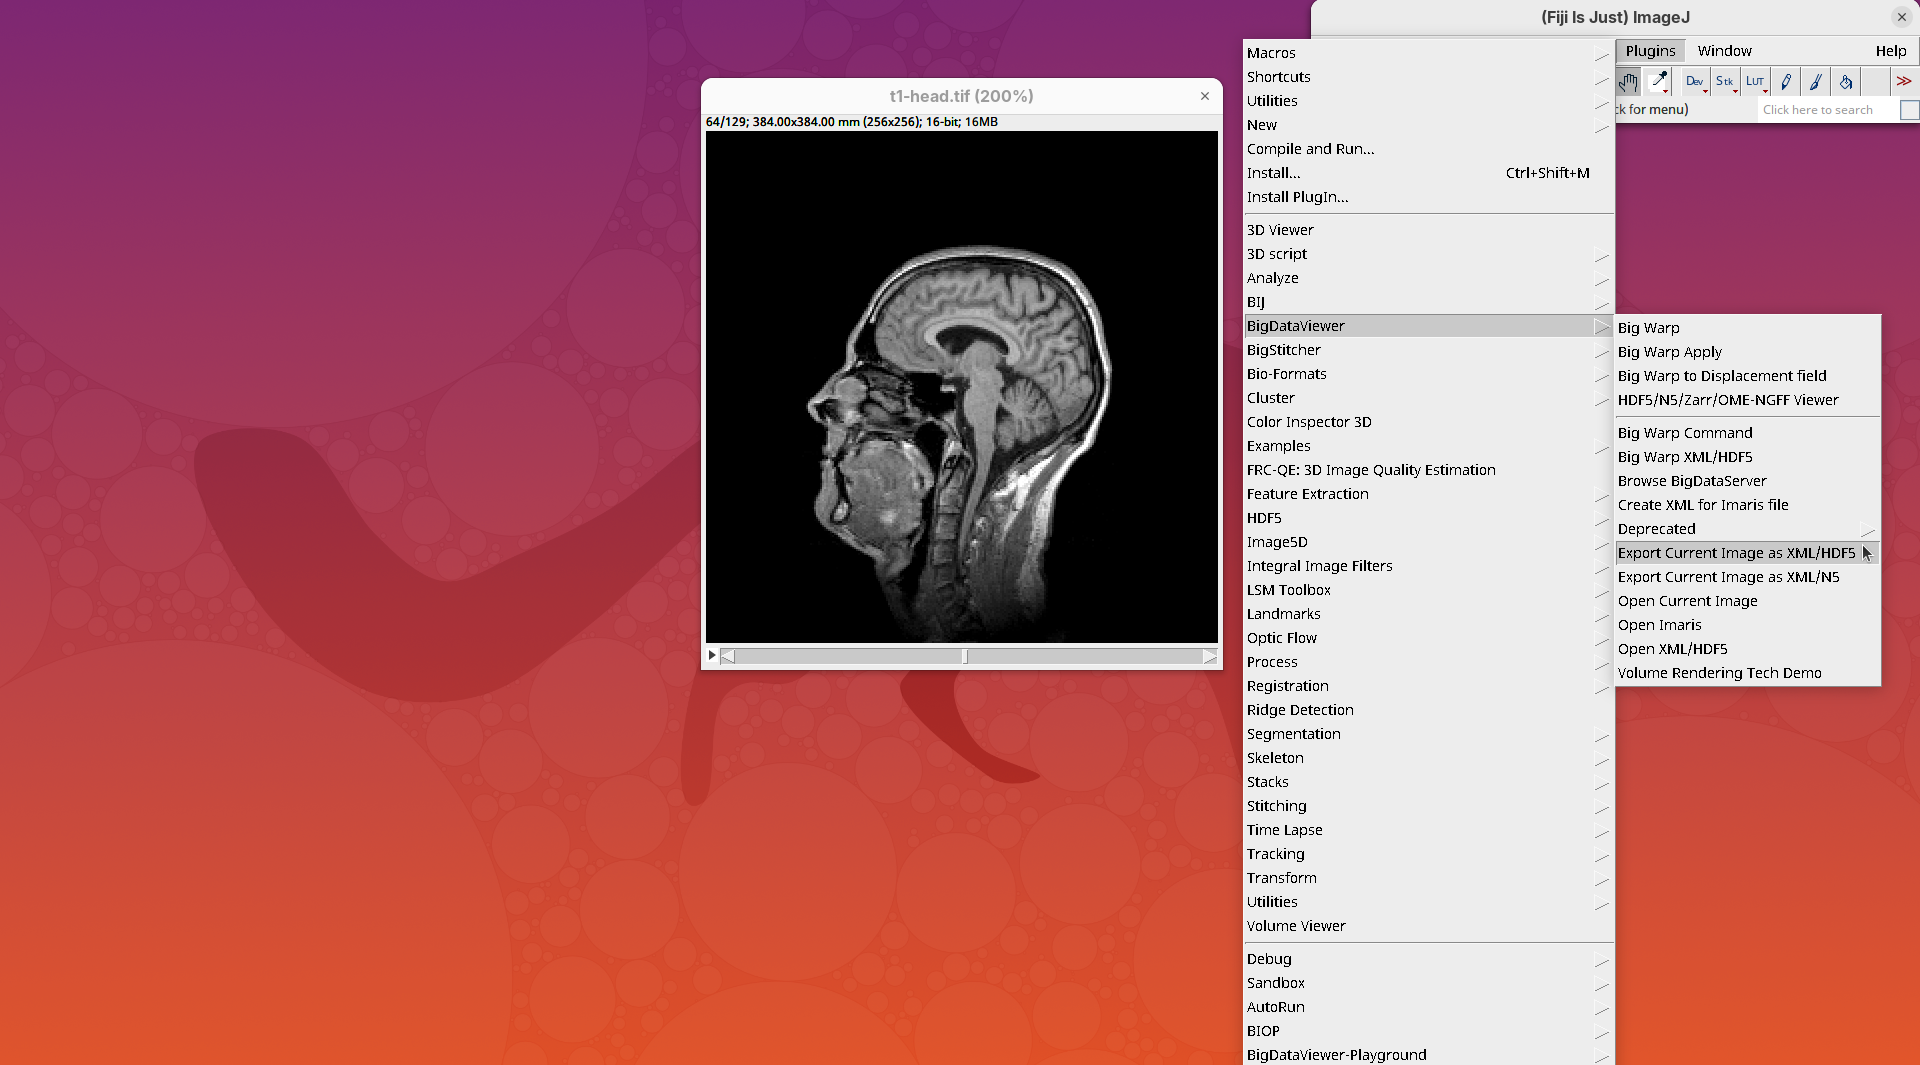

BigDataViewer

BigDataViewer (Pietzsch et al. 2015) is one of the most important tools for visualizing large, multidimensional datasets. It provides a simple and intuitive interface and shortcuts to swiftly navigate through your sample even on a regular laptop. This is possible because of the underlying file format used by BigDataViewer: the XML/HDF5 combo. Therefore, before opening the plugin, we must convert our dataset.

- Go to

Plugins>BigDataViewer>Export Current Image as XML/HDF5.

A dialog with export options will open.

- Under

Export path, click onBrowseto select the output directory fort1-head.xml.

The export process will start. Since this is a small dataset, it’ll be fast. But, for large datasets, this can take hours.

When done, you will find two new files in your working directory: t1-head.xml and t1-head.h5.

The XML file stores metadata information about the image. The HDF5 file stores actual image data. These two files will always be in a pair. To open the XML/HDF5:

- Go to

Plugins>BigDataViewer>Open XML/HDF5and select thet1-head.xml.

The BigDataViewer interface will open showing an optical section of the head sample.

Getting familiar with BigDataViewer is an essential skill for navigating large 3D datasets. It’ll also be important for the multiview registration pipeline. So, take the time to learn the basic commands and shortcuts. It is nicely intuitive. The BigDataViewer’s page on the ImageJ Docs has the official documentation and we can also go to Help > Show Help for an up-to-date overview.